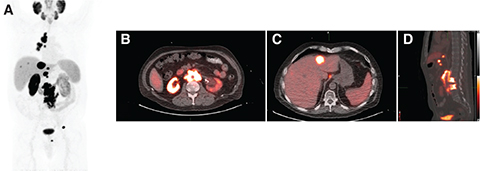

ROLE OF PSMA PET IMAGING

Lesion-specific PSMA expression is evaluated with PSMA PET imaging and is a key determinant for PSMA RLT eligibility. For PSMA RLT to be beneficial, metastatic lesions must demonstrate sufficient expression of PSMA (Figure 1). Patients whose metastatic lesions lack significant PSMA expression should not be considered for PSMA RLT, as PSMA receptor expression is required for treatment target localization (Figure 2). Pretreatment PSMA PET may also contain important prognostic information that has been shown to correlate with the degree of response and overall benefit of PSMA RLT. However, there are different definitions of what constitutes PSMA-positive and PSMA-negative disease in currently published PSMA RLT trials (Tables 1 and 2).

Fig 2

Figure 2. An 82-year-old man with metastatic prostate cancer, but with limited PSMA expression of disease, ineligible for 177Lu- PSMA-617 RLT. A. Maximum intensity projection image of 18F-PyL PSMA PET/CT; B. axial CT image of the chest demonstrating one osteoblastic rib lesion and mild uptake in the sternal body and a right-sided rib; C. axial PSMA PET image demonstrating uptake related to the osteoblastic rib lesion and mild uptake in the sternal body and a right-sided rib; D. fused PET/CT images of B and C; E. axial CT image demonstrating an osteoblastic right iliac bone lesion; F. PSMA PET image demonstrating limited uptake associated with the osteoblastic lesion; G. fused images of E and F.

To identify potential PSMA-negative disease, patients should undergo contrast-enhanced CT or MRI of the abdomen and pelvis within a reasonable timeframe surrounding PSMA PET imaging. Treatment may be appropriate for patients with heterogeneous disease on PSMA PET, especially if most of the disease is PSMA positive and the patient has exhausted all other therapeutic options.